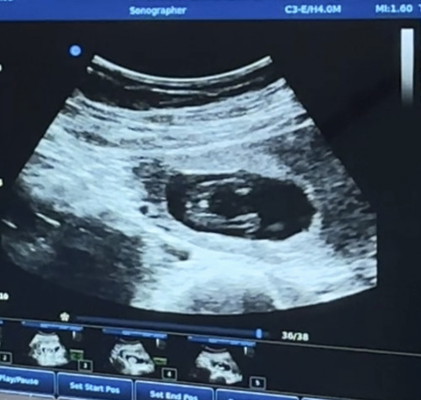

เบบี๋ 15w ไปอัลตราซาวด์ดูเพศ

สอบถามแม่ๆค่า แบบนี้ ผู้หญิง รึ ผู้ชายคะ